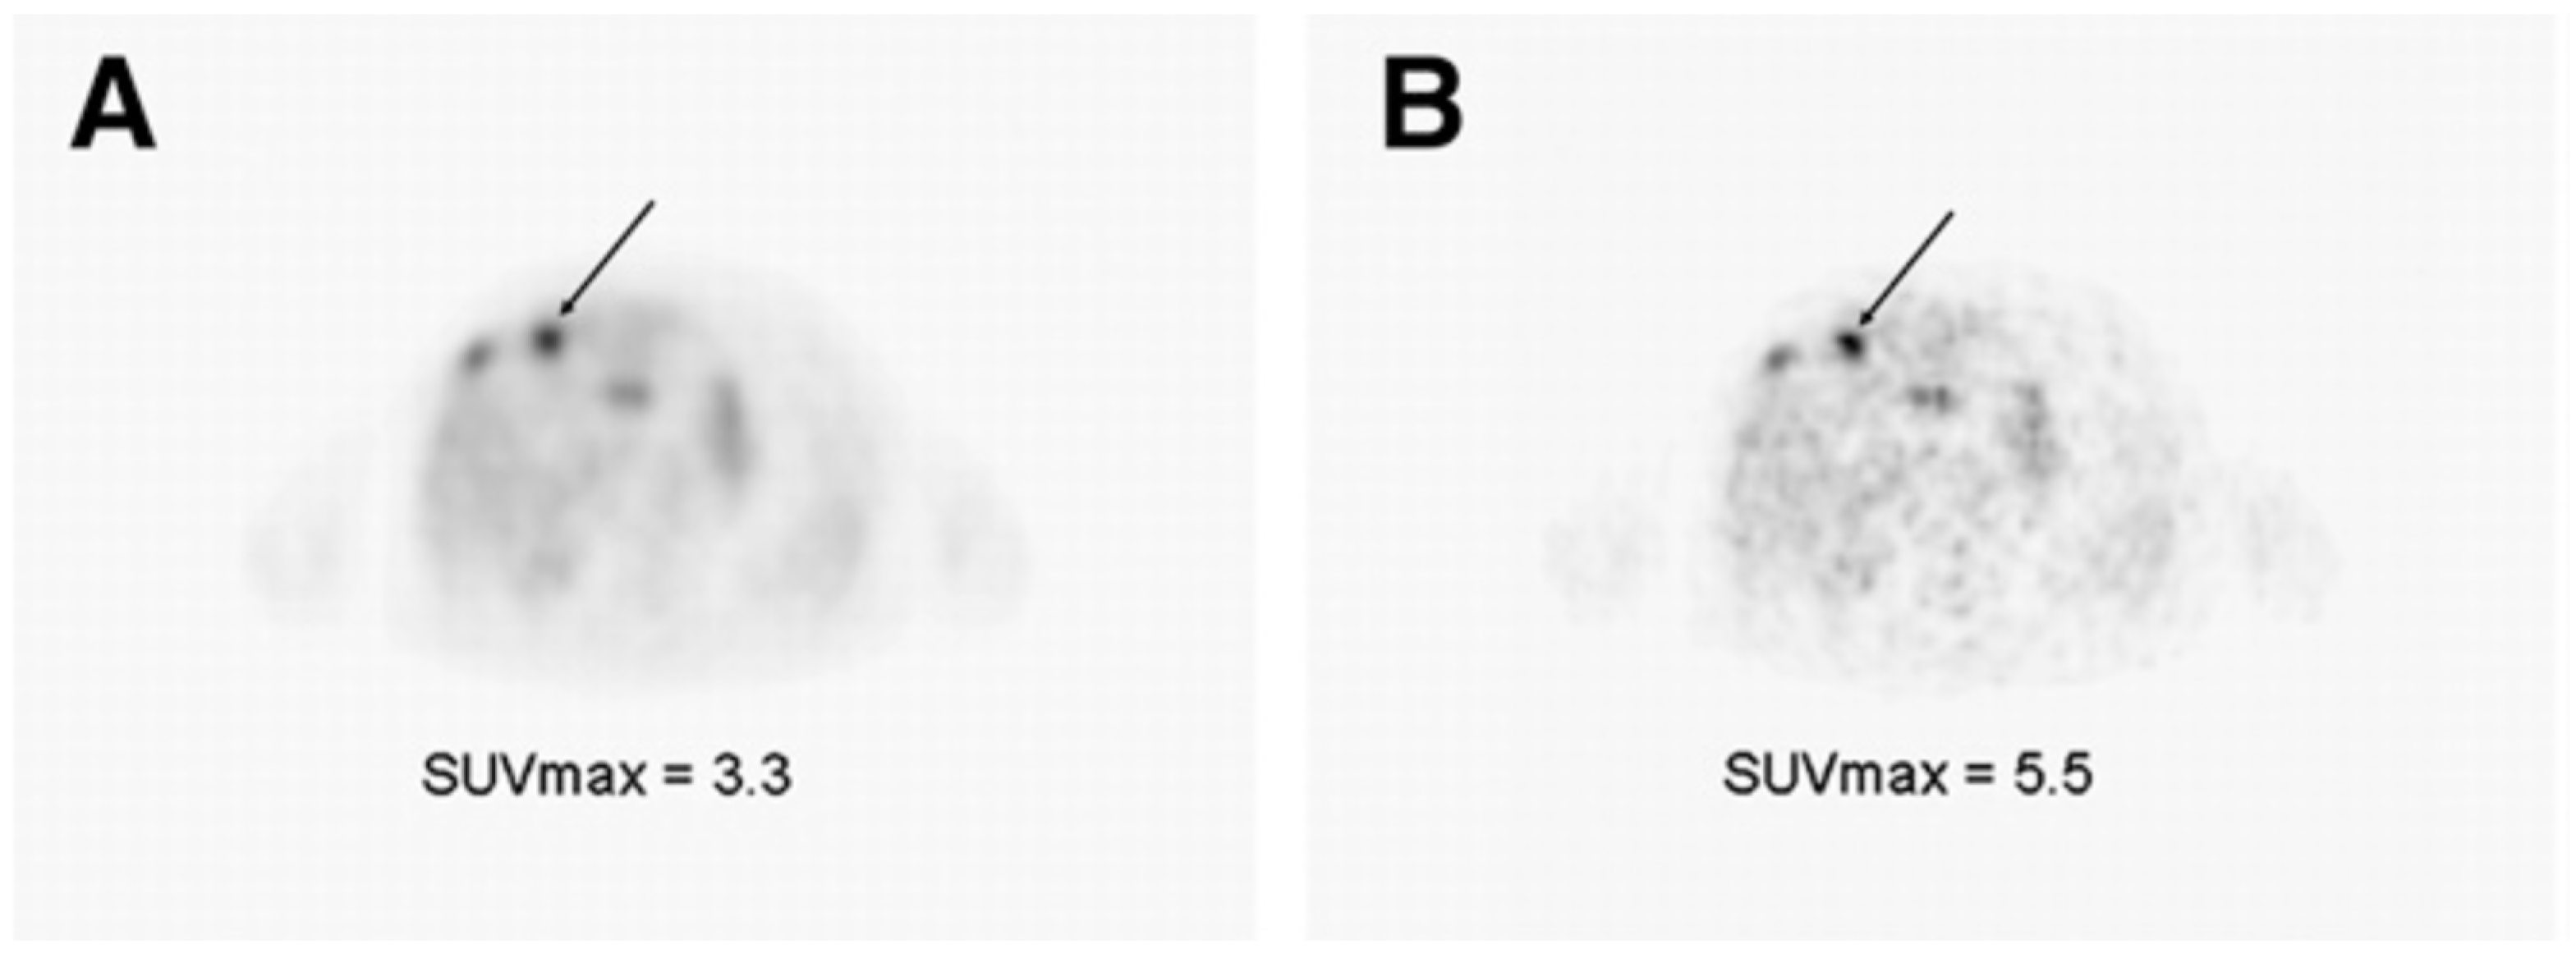

- Verwer, E.E.; Boellaard, R.; Van Der Veldt, A.A.M. Positron emission tomography to assess hypoxia and perfusion in lung cancer. World J. Clin. Oncol. 2014, 5, 824–844. [Google Scholar] [CrossRef]

- Novruzov, E.; Mori, Y.; Antke, C.; Dabir, M.; Schmitt, D.; Kratochwil, C.; Koerber, S.A.; Haberkorn, U.; Giesel, F.L. A role of non-FDG tracers in lung cancer? Semin. Nucl. Med. 2022, 52, 720–733. [Google Scholar] [CrossRef]

- Perez, R.C.; Kim, D.; Maxwell, A.W.P.; Camacho, J.C. Functional imaging of hypoxia: PET and MRI. Cancers 2023, 15, 3336. [Google Scholar] [CrossRef]